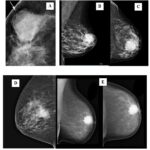

Anexo 1. Imágenes mamográficas de CMTN

Características mamográficas del CMTN

Los resultados de las características mamográficas en nuestra población con CMTN (n = 17) se describen de la siguiente manera: la mayoría presentó un tejido fibroglandular ACR B (n = 10), lo que equivale al 60% de la muestra total. Le siguió un ACR A (n = 3). En cuanto a la descripción de los nódulos, se reportaron como ovalados en el 70% de los casos, con márgenes circunscritos en el 47%. Además, se observó que eran hiperdensos en el 76% de los casos y no presentaban calcificaciones asociadas (100%). No se encontró evidencia de adenopatías axilares ni lesiones asociadas mediante este método diagnóstico.

Los hallazgos radiológicos, tanto en mamografía como en ecografía, describen características comunes de los nódulos en pacientes con CMTN, incluyendo la forma ovalada, los márgenes circunscritos o lobulados, la hipoecogenicidad y la ausencia de hallazgos acústicos posteriores. Estos resultados subrayan la importancia de la evaluación exhaustiva de las características mamográficas y ecográficas en el diagnóstico y la estratificación de los CMTN, que presentan concordancia con lo descrito en la bibliografía médica actual revisada.

Los hallazgos imagenológicos en mamografías, ecografías y resonancias magnéticas en pacientes con CMTN concuerdan con la bibliografía médica actual, lo que respalda la utilidad de estas técnicas para el diagnóstico y caracterización de los CMTN.